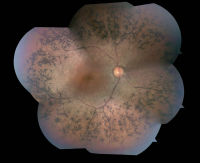

NEW YORK, NY (Nov. 14, 2016)—Columbia University Irving Medical Center (CUIMC) researchers have demonstrated that vision loss associated with a form of retinitis pigmentosa (RP) can be slowed dramatically by reprogramming the metabolism of photoreceptors, or light sensors, in the retina. The study, conducted in mice, represents a novel approach to the treatment of RP, in which the therapy aims to correct downstream metabolic aberrations of the disease rather than the underlying genetic defect.

RP, an inherited form of vision loss, is caused by genetic defects that lead to the breakdown and loss of rods, the photoreceptors in the retina that enable peripheral and night vision. Over time, the deterioration of rods compromises the function of cones, the color-sensing photoreceptors. People with RP start to experience vision loss in childhood, and many are blind by the time they reach adulthood. Currently, there is no cure or effective treatment for RP, which affects about 1 in 4,000 people worldwide.